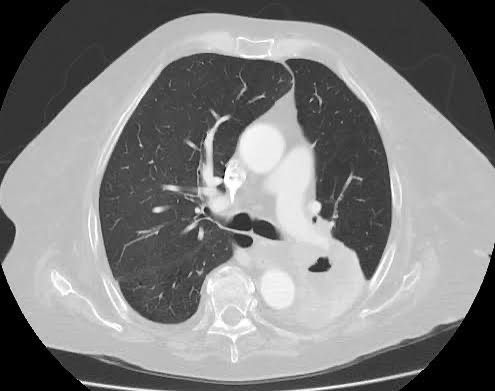

CT scan showing lung cancer

VS-EDGE (Visual-Semantic Explanations for Diagnostic Guidance) aims to bridge the gap between research Computer-Aided Diagnosis (CAD) systems and clinical use by developing explainable CAD systems for lung cancer and connecting image features extracted computationally with semantic understanding.